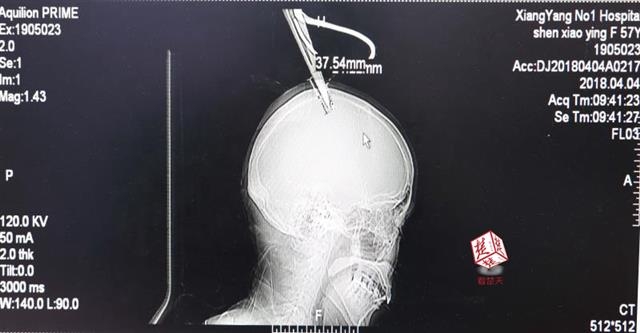

醫(yī)生檢查發(fā)現(xiàn),剪刀刀尖斜嵌在沈某顱骨里,離腦髓只有兩三毫米。所幸是斜著插進去,如果是垂直刺入,很有可能造成癱瘓。

4月4日清晨,襄陽市樊城區(qū)太平店鎮(zhèn)57歲的農村婦女沈某,在采摘香椿嫩芽時,綁在竹桿上的剪刀因竹子腐朽不慎折斷,剪刀斜插入頭顱。經過及時搶救,目前脫離生命危險。

醫(yī)生檢查發(fā)現(xiàn),剪刀刀尖斜嵌在沈某顱骨里,離腦髓只有兩三毫米。所幸是斜著插進去,如果是垂直刺入,很有可能造成癱瘓。最終經過手術,剪刀被取出,沈某目前仍在ICU進一步觀察。